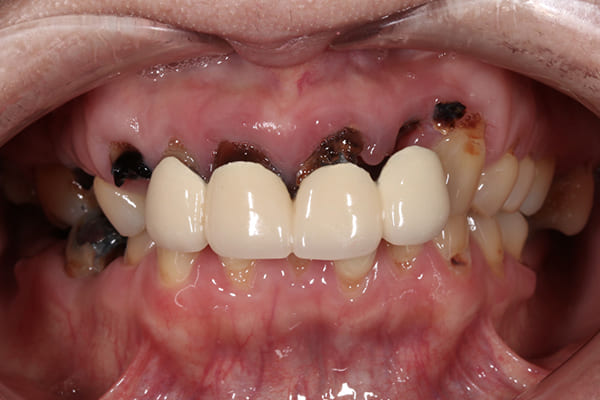

初診時の口腔内

「見た目を治したい」と来院された50代の女性の患者様です。

お口全体に虫歯がかなり進行しており、噛み合わせのバランスも崩れてる状態でした。

こちらが初診時の状態です